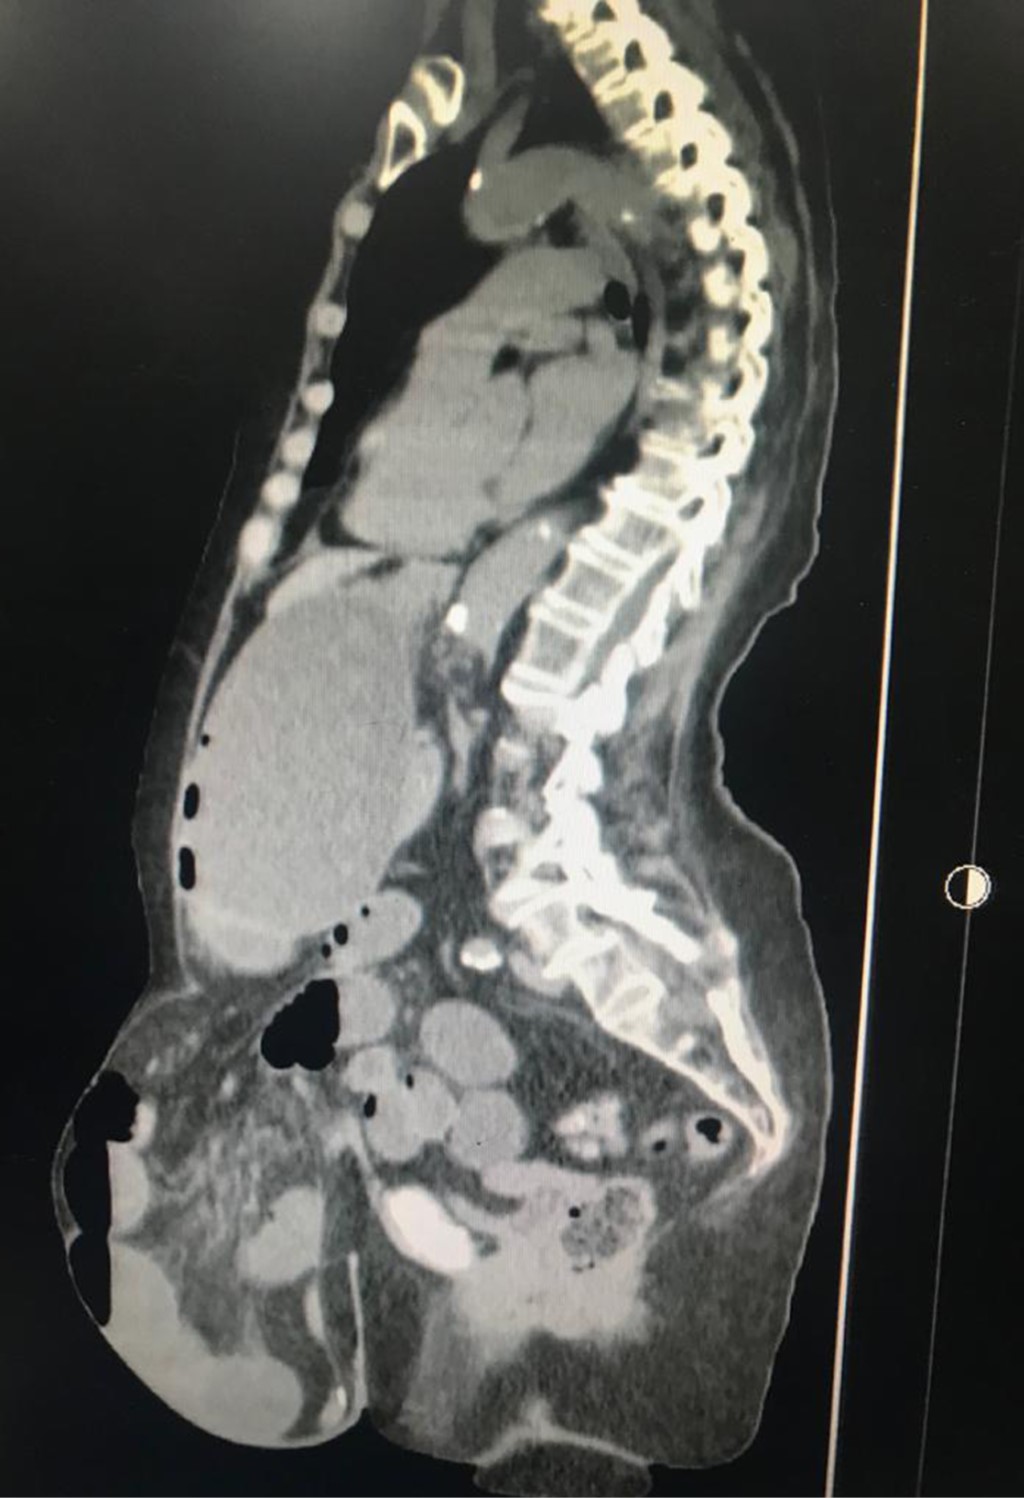

Giant incisional hernia and intestinal occlusion a medical-surgical challenge

Complex hernias with "loss of domain" are giant hernias with chronic wall defects. The separation of components is one of the techniques used in large abdominal hernias. We present the case of an 86-year-old female with a 43-year-old hernia with intestinal occlusion, laparotomy, anastomosis, adherenciolosis, and component separation with mesh placement; her evolution was favorable with satisfactory postoperative follow-up functionally without complications. The literature declares the surgeon's own experience to be the most important prognostic factor for the outcome of the surgical intervention.

Figure 1

Figure 2

Figure 3

Figure 4